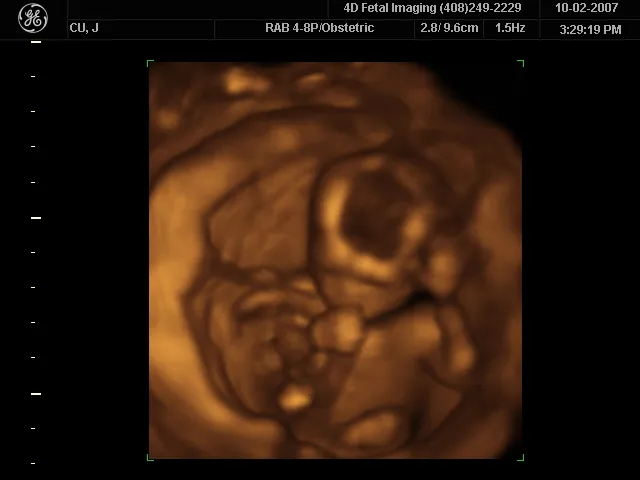

The most common ultrasound applications produce an image like that shown in Figure 17.43. The speaker-microphone broadcasts a directional beam, sweeping the beam across the area of interest. This is accomplished by having multiple ultrasound sources in the probe’s head, which are phased to interfere constructively in a given, adjustable direction. Echoes are measured as a function of position as well as depth. A computer constructs an image that reveals the shape and density of internal structures.

The first part of the diagram shows an ultrasound device scanning a woman’s abdomen. The second part of the diagram is an ultrasound scan report of the abdomen.

Figure 17.43 (a) An ultrasonic image is produced by sweeping the ultrasonic beam across the area of interest, in this case the person's abdomen. Data are recorded and analyzed in a computer, providing a two-dimensional image (credit: COD Newsroom, Flickr). (b) Ultrasound image of 12-week-old fetus. (credit: Public Health Image Library, CDC)